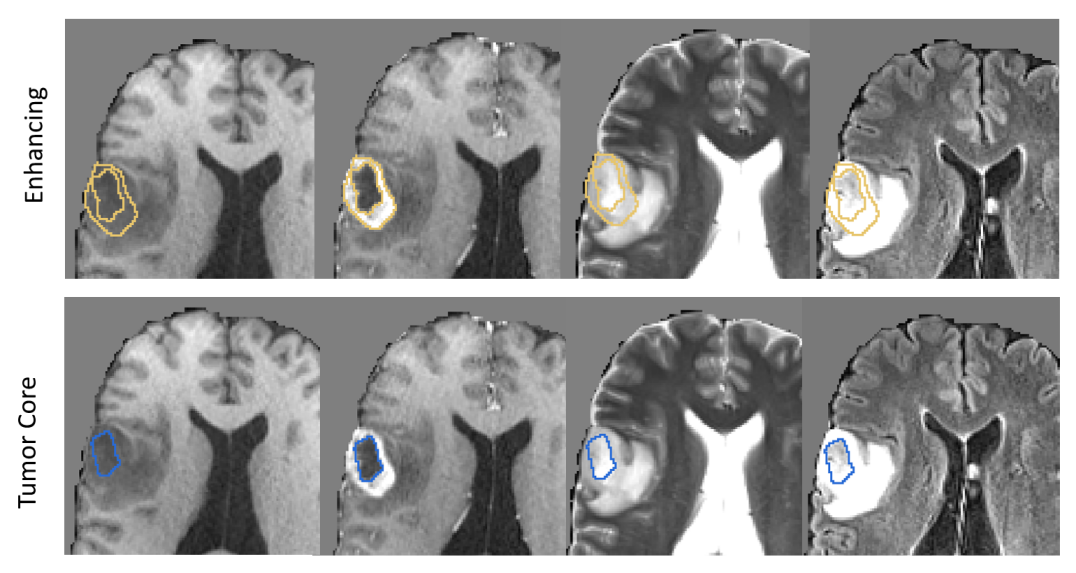

Figures 2 and 3 shows example segmentation results for whole tumor, enhancing tumor and tumor core. Results over the BraTS validation set are shown in Figure 4. These results reflect those reported via the online leaderboard on 8th September 2017 444https://www.cbica.upenn.edu/BraTS17/lboardValidation.html. Out of the 61 entrants, our algorithm places 21st for whole tumor, 16th for enhancing tumor and 28th for tumor core.

Refer to caption

Figure 3: Example segmentation results for enhancing tumor and tumor core.